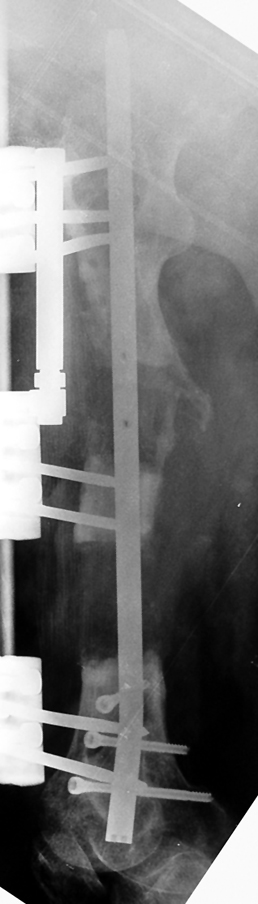

The duration of external fixation (external fixation index) depends on the amount of distraction required, and the extremity is prone to complications during this period. After the distraction phase is completed, the external fixator remains in place during the consolidation phase, which lasts twice as long as the distraction phase; but this period is hardly tolerated. If the external fixator is removed before sufficient consolidation is achieved, fractures, deformity and shortness will be the result. In our department, ‘lenghthening over nail’ method is used in order to decrease the external fixation index and increase patient comfort and activity level. In this method, the intramedullary nail is statically locked after the completion of the distraction phase, and external fixator is removed. The extremity is stabilized by the intramedullary nail during consolidation phase. In this way, complications due to long external fixation index or early removal of the external fixator are avoided.